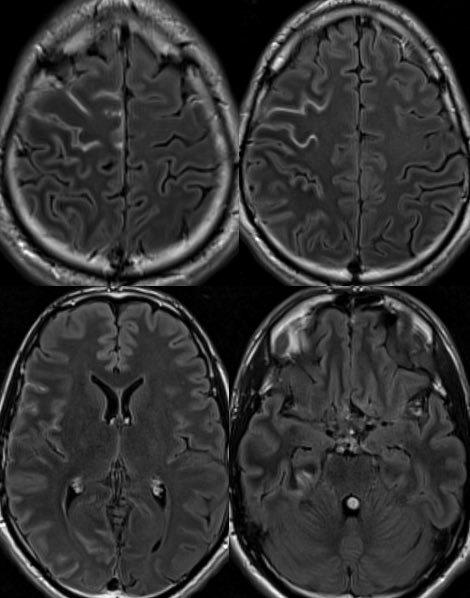

🔷Typical Imaging of MOG-AAD:

▶️BRAIN findings: Occur in <50% of patients though tend to involve the deep gray matter and infratentorium (particularly in children)

▶️Patterns include ADEM-like or CLIPPERS-like imaging features

▶️Leptomeningeal enhancement can also be seen in association with FUEL & FLAMES x.com

🔷A distinct subtype/clinicoradiographic syndrome of MOGAD is a cortical encephalitis presenting with headache, fever and seizures known as FLAMES of MOGAD🔥

🔷When the predominant imaging features are leptomeningeal enhancement with little to no cortical involvement, this is considered FUEL of MOGAD ⛽️ x.com

▶️Imaging: Unilateral (more common) or b/l cortical swelling (🔥) or isolated leptomeningeal enhancement (⛽️) +/- other features of MOGAD